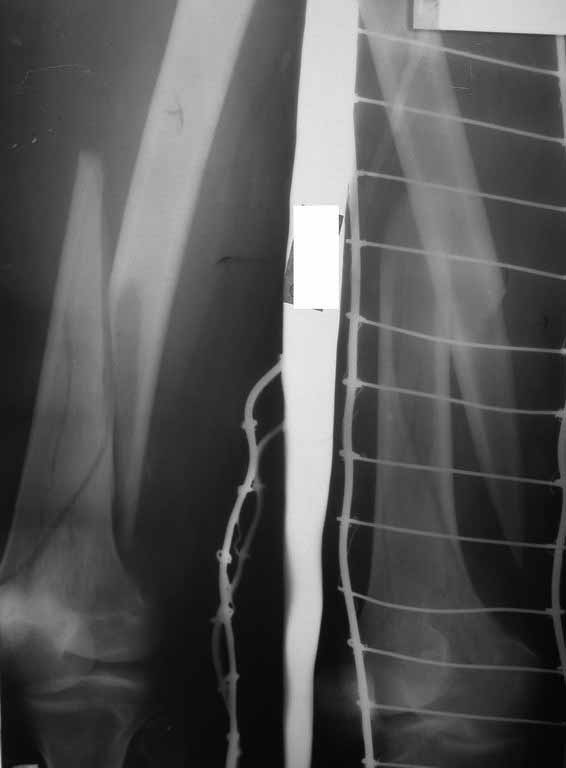

Представляю вам один из наших недавних случаев выполнения малоинвазивного остеосинтеза бедренной кости обычной пластиной 95 градусов. Длина восстановлена с помощью дистрактора (по сути это основная и б(о)льшая часть репозиции). Произведено два небольших доступа, проведена спица направитель. Рентген-контроль для подтверждения достаточной длины/оси (ЭОП использовался в другой операционной). Создание туннеля обратной стороной фиксатора. Поворот фиксатора, введение клинка по спице. Фиксация проксимального и дистального концов пластины.

Получилось очень симпатично, поздравляю и восхищаюсь мастерством.

Хотя закрытый остеосинтез блокированным гвоздем выглядит технически проще, особенно при диафизарных переломах. Не говоря о биомеханических преимуществах внутрикостного имплантата, еще меньшей инвазивности, возможности динамизации при проблемах со сращением... Стоимость гвоздей и пластин сопоставимая, на рынке есть масса отечественных предложений.